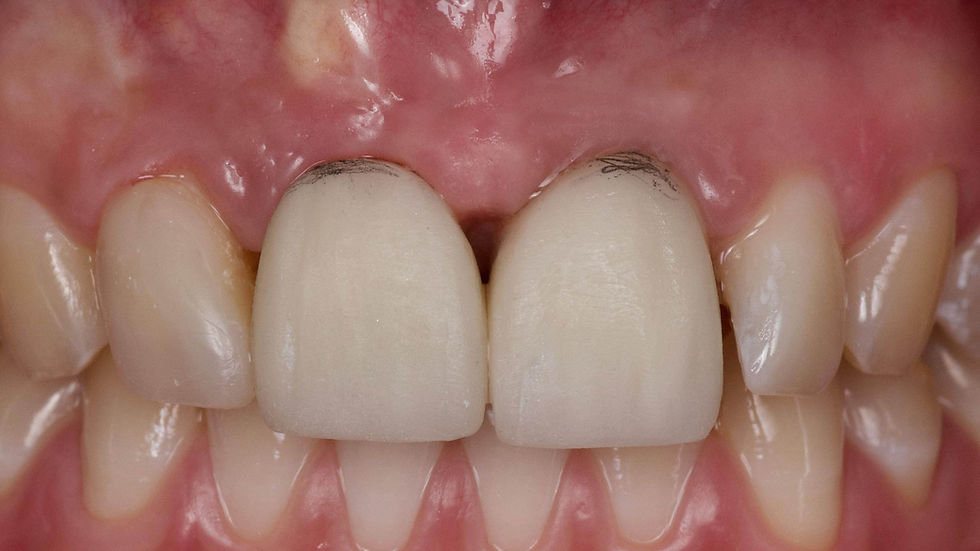

The intraoral picture highlights the resorption around the element 1.1 and the inaccuracy of the existing prosthetic restoration.

The comparison between the intraoral pictures and the bone volumes revealed at the CBCT examination highlights the severe vestibular bone atrophy and the irregularity of the marginal crest.